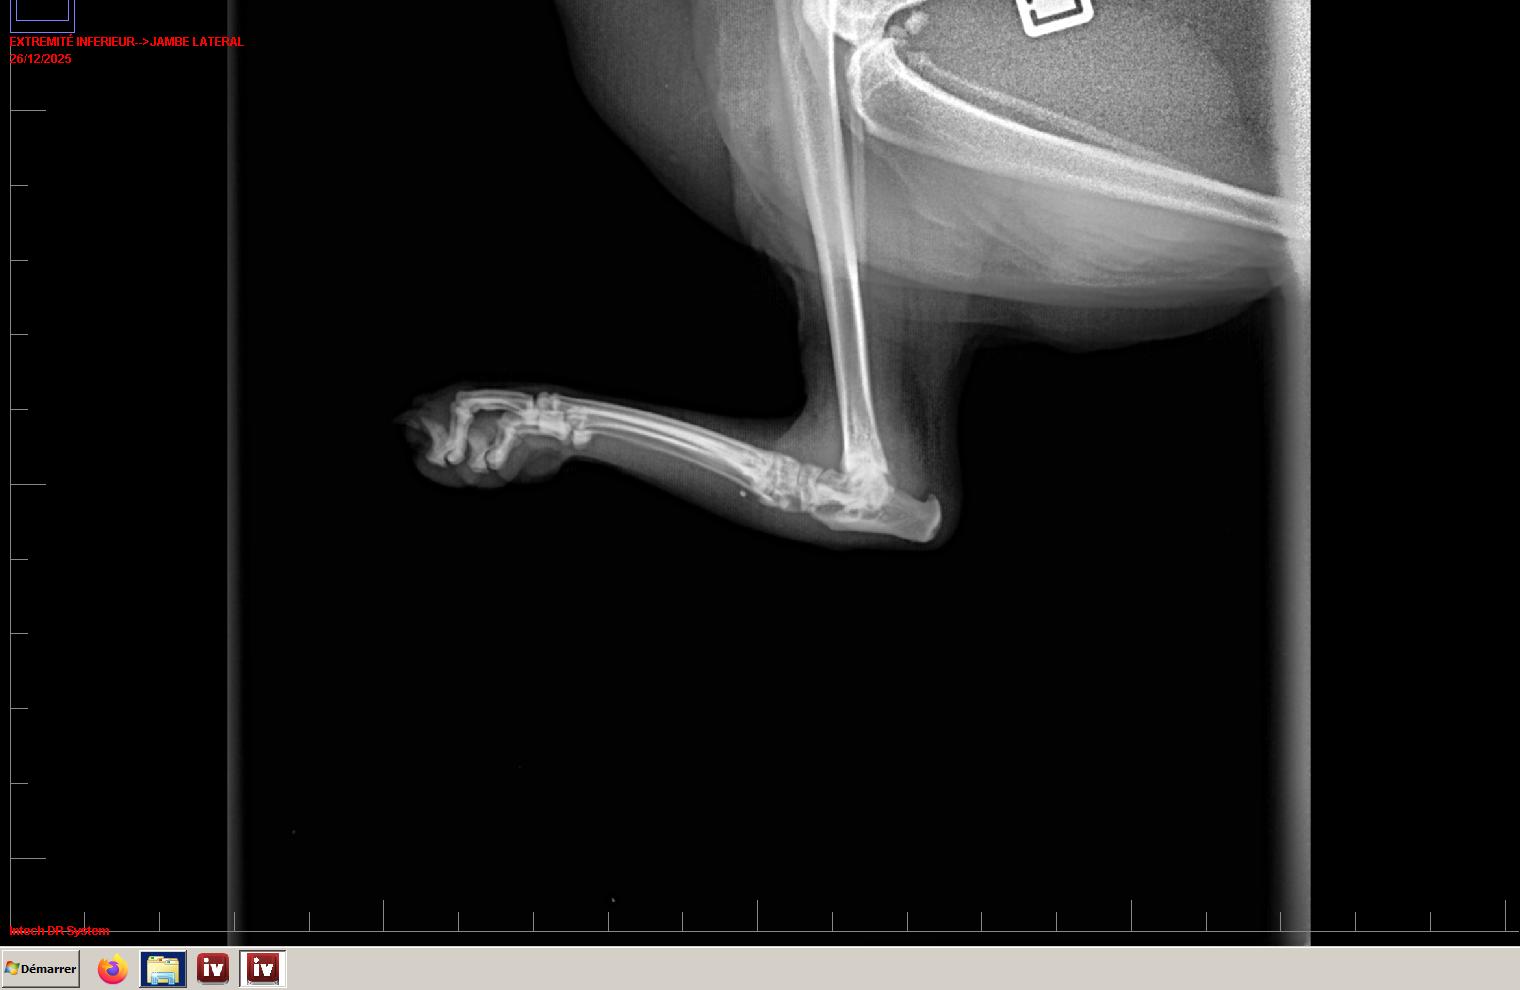

- De décrire les incidences standards chez les oiseaux et reptiles.

- D’expliciter la raison de l’utilisation d’un faisceau de RX à axe horizontal chez les reptiles.

- De lister les particularités anatomiques dominantes chez les oiseaux et les reptiles.

- D’identifier les organes visibles sur une radiographie d’oiseau et de reptile.